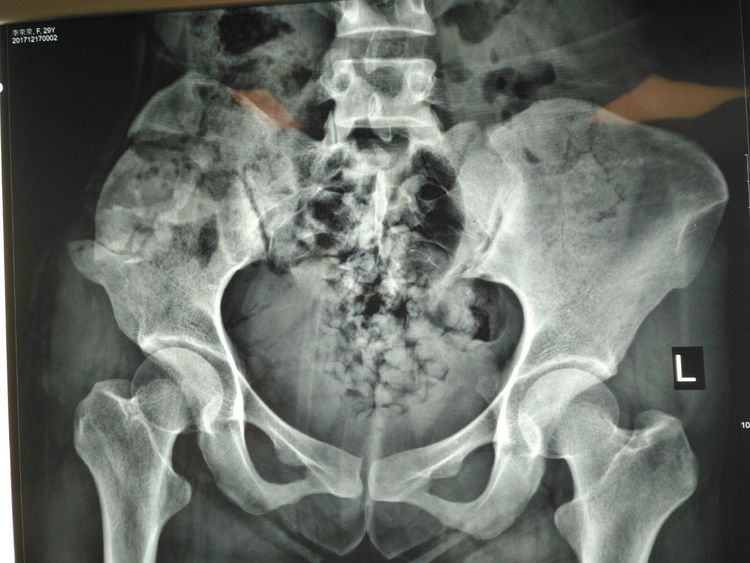

術(shù)前X線檢查